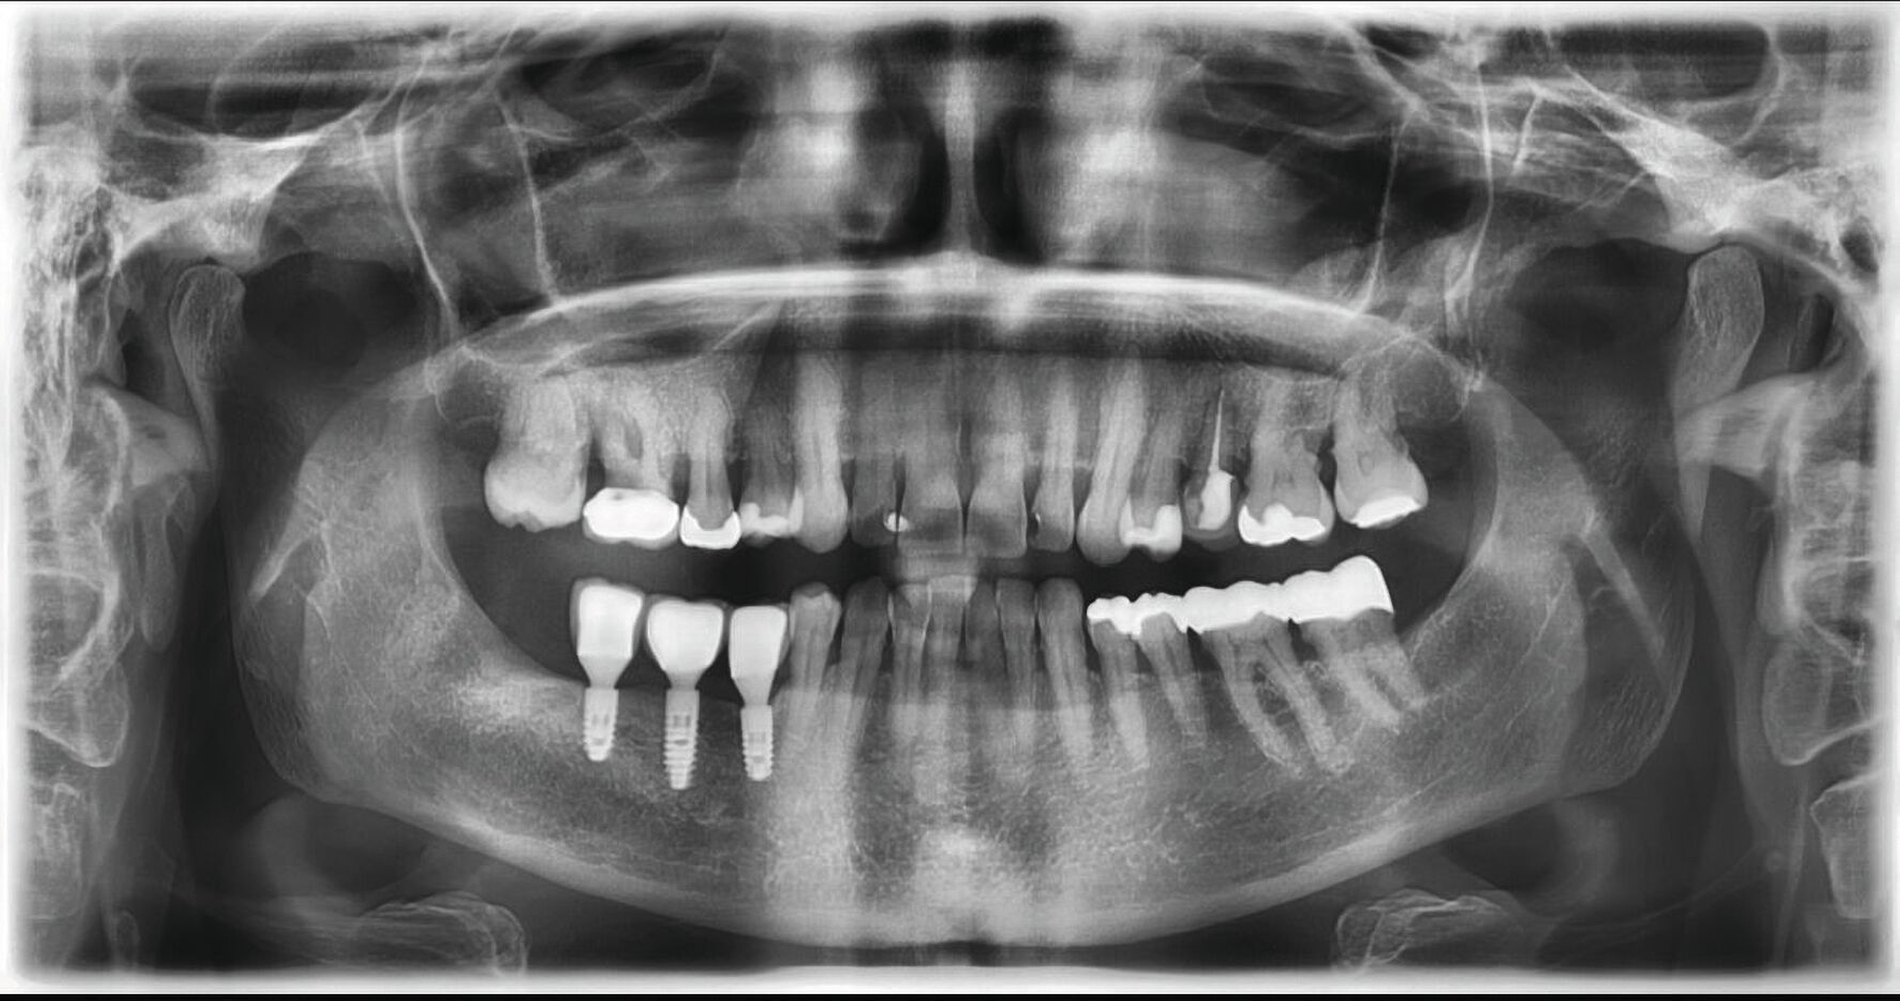

Das präoperative OPG zeigte einen generalisierten horizontalen und an den Zähnen 16 und 26 auch einen vertikalen Knochenabbau, Konkremente insbesondere im zweiten und im dritten Quadranten und in der Unterkieferfront, einen Füllungsverlust an 22, eine regelrechte Wurzelkanalbehandlung an Zahn 25, aber keine weiteren Auffälligkeiten in den umgebenden radiologischen Strukturen (Abbildung 2). Unter antibiotischer Abschirmung wurde der nekrotische Knochen einschließlich des Zahnes 25 bis zum vitalen, durchbluteten Gewebe in Lokalanästhesie abgetragen (Abbildung 3). Der Wundverschluss erfolgte mittels eines Dehnungslappens durch Periostschlitzung (Abbildung 4). Es folgte eine detaillierte Instruktion zur postoperativen Wundschonung. Eine Röntgenkontrolle wurde postoperativ durchgeführt (Abbildung 5).